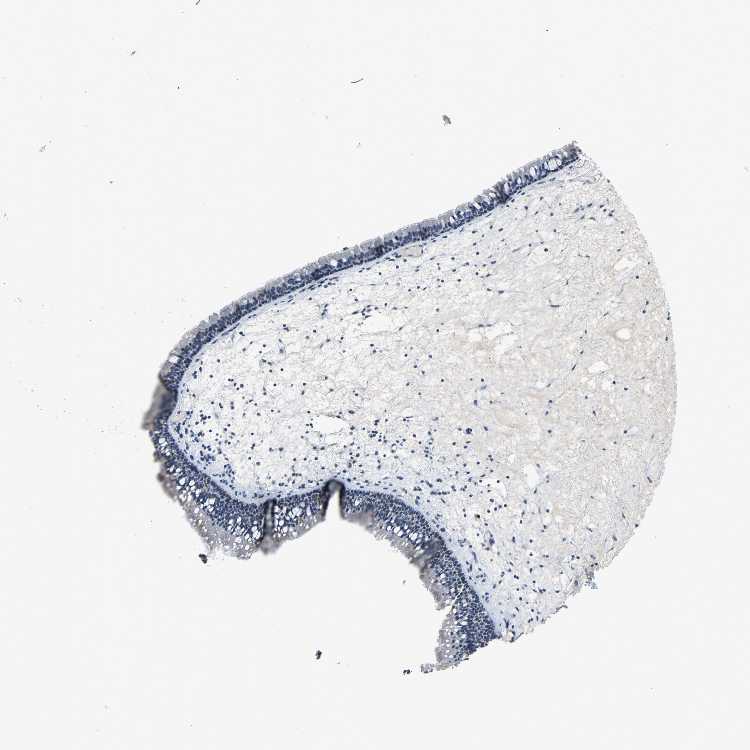

NASOPHARYNX - Antibody stainingi

Antibody staining in the annotated cell types in the current human tissue is reported as not detected, low, medium, or high, based on conventional immunohistochemistry profiling in selected tissues. This score is based on the combination of the staining intensity and fraction of stained cells.

Each image is clickable and will lead to virtual microscopy that enables deeper exploration of all samples and also displays staining intensity scores, fraction scores and subcellular localization as well as patient and tissue information for each sample.

Antibody CAB004282

Respiratory epithelial cells Not detected